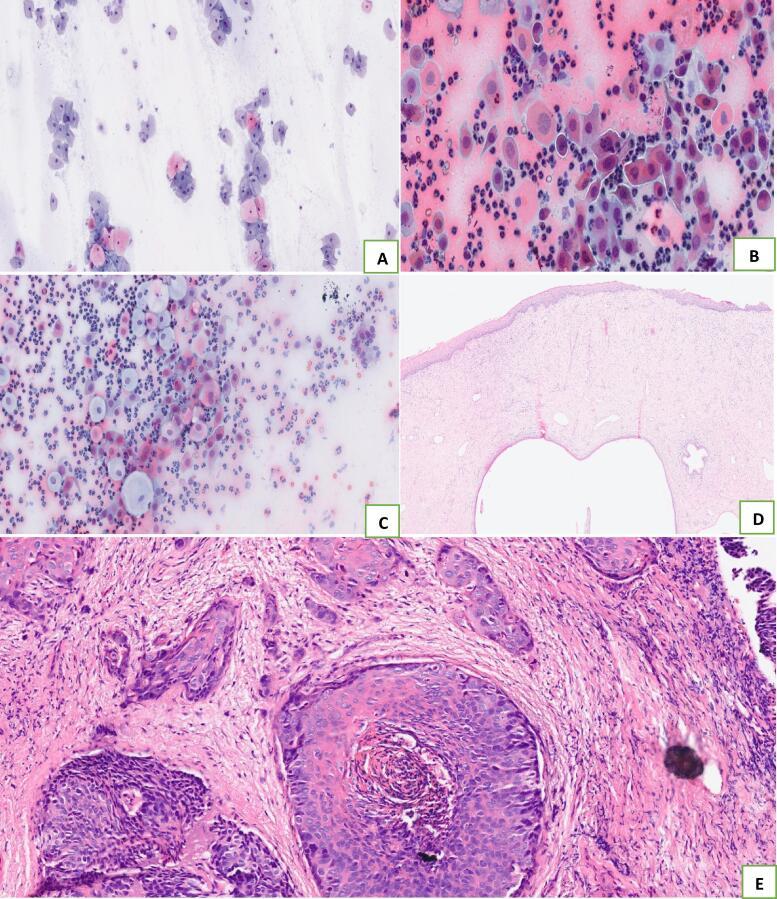

MATERIAL AND METHODS

We recruited 90 cervical intraepithelial neoplasia (CIN) cases, 90 cervical cancer (CC) cases before treatment and 90 controls. Clinical and demographic data were recorded. Serum P16ink4A concentrations were measured by quantitative Elisa. Cases were confirmed with cytology and/or histology. Descriptive statistics and logistic regression were done with STATA 17 and P-values of <0.05 were considered statistically significant.

我们招募了90例宫颈上皮内瘤变(CIN)病例、90例治疗前宫颈癌(CC)病例和90例对照。记录临床和人口统计学数据。通过定量酶联免疫吸附测定法测量血清P16ink4A浓度。病例通过细胞学和/或组织学确诊。使用STATA 17进行描述性统计和逻辑回归分析,P值<0.05被认为具有统计学意义。